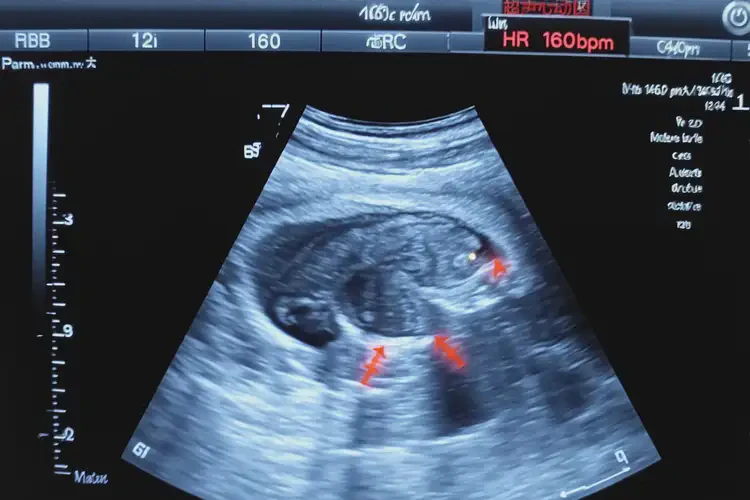

孕15周4天胎心率160左右寶寶還能要嗎

胎心率160次/分鐘在正常范圍內(nèi),寶寶可以要。

胎心率是指胎兒心臟每分鐘跳動(dòng)的次數(shù),是評(píng)估胎兒健康狀況的重要指標(biāo)之一。在孕15周4天時(shí),胎兒的胎心率在160次/分鐘左右是正常的。根據(jù)醫(yī)學(xué)研究和臨床經(jīng)驗(yàn),胎兒的正常胎心率范圍為120-160次/分鐘。胎心率160次/分鐘的寶寶是健康的,可以繼續(xù)妊娠。

孕15周4天胎心率160左右寶寶還能要嗎(圖1)